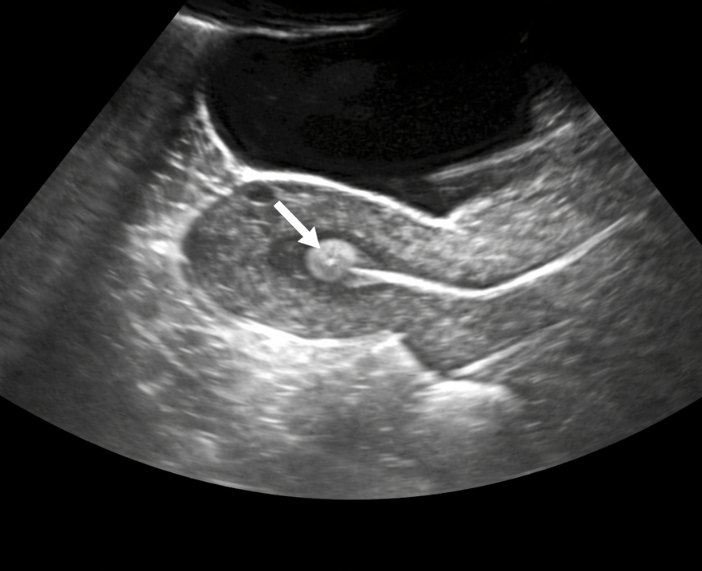

In Vitro Fertilization (IVF)

IVF is a process where eggs and sperm are combined outside the body in a lab. The fertilized embryo is then transferred into the uterus. It is widely used for various infertility issues. IVF offers high success rates.

Embryo Transfer

Embryo transfer is the final step of IVF where embryos are placed into the uterus. It is a simple and painless procedure. The goal is to achieve implantation and pregnancy. Timing is crucial for success.